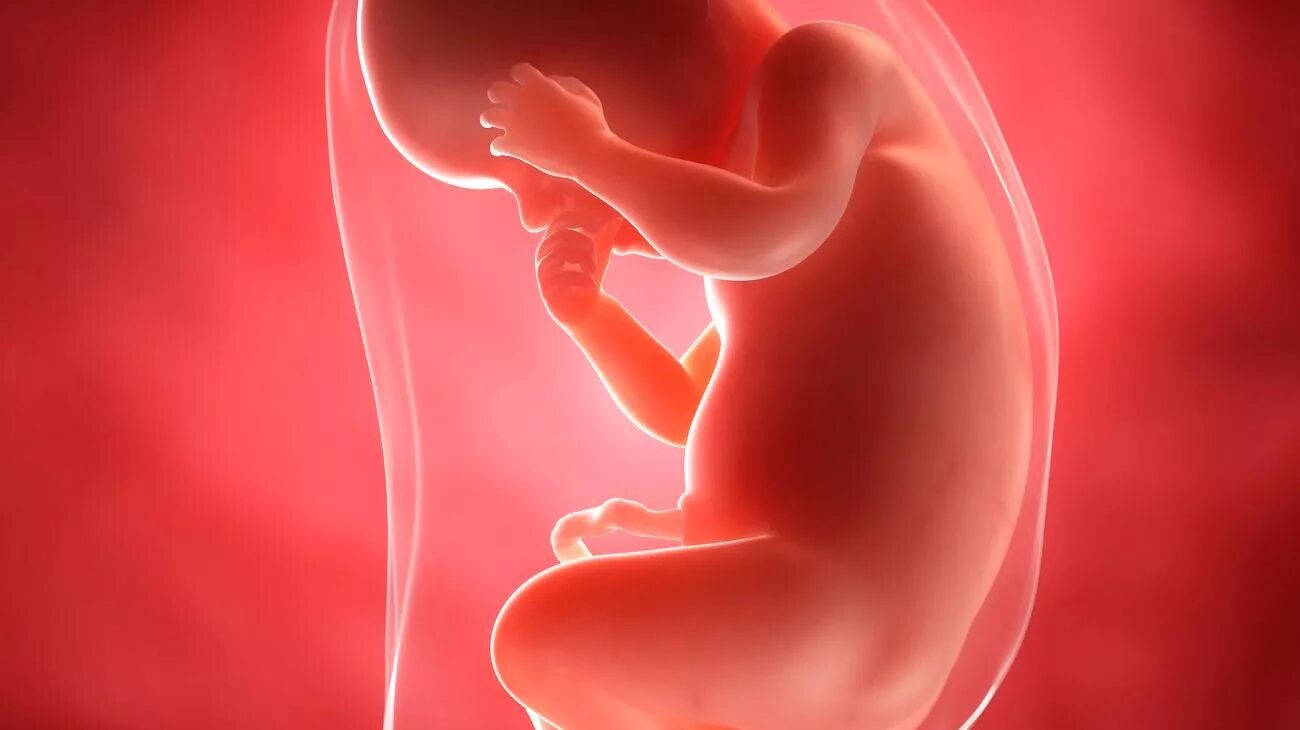

Развития плода 30 недель